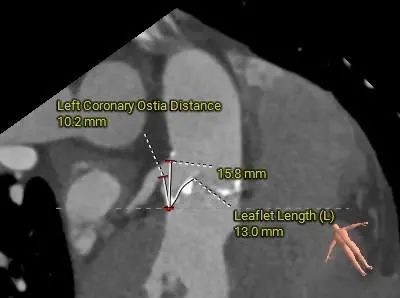

冠脉评估:

左冠开口高度较低,瓣叶略冗长

根部结构较小,冠脉阻挡风险偏高